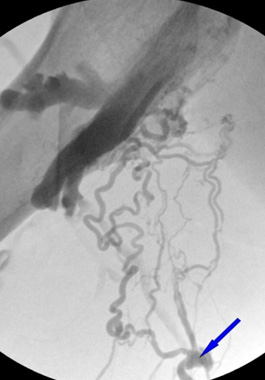

对于起始部逆流,通过使大隐静脉与深层静脉相交处的两个血管呈现为接近 0 度,水平紧密封堵,以此预防复发。